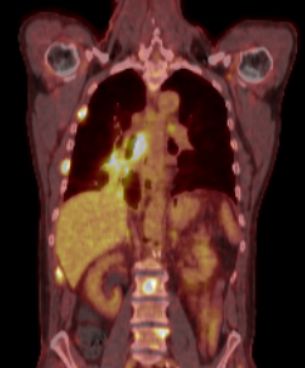

PET Primärtumor im rechten unteren Hilus, mediastinale Lymphknoten, Metastasen in 3 Rippen rechts sind erkennbar.